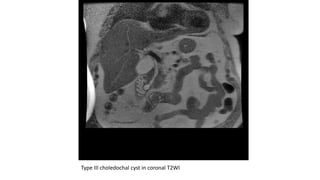

Type III choledochal cyst in coronal T2WI

Type III choledochalcyst in coronal T2WI